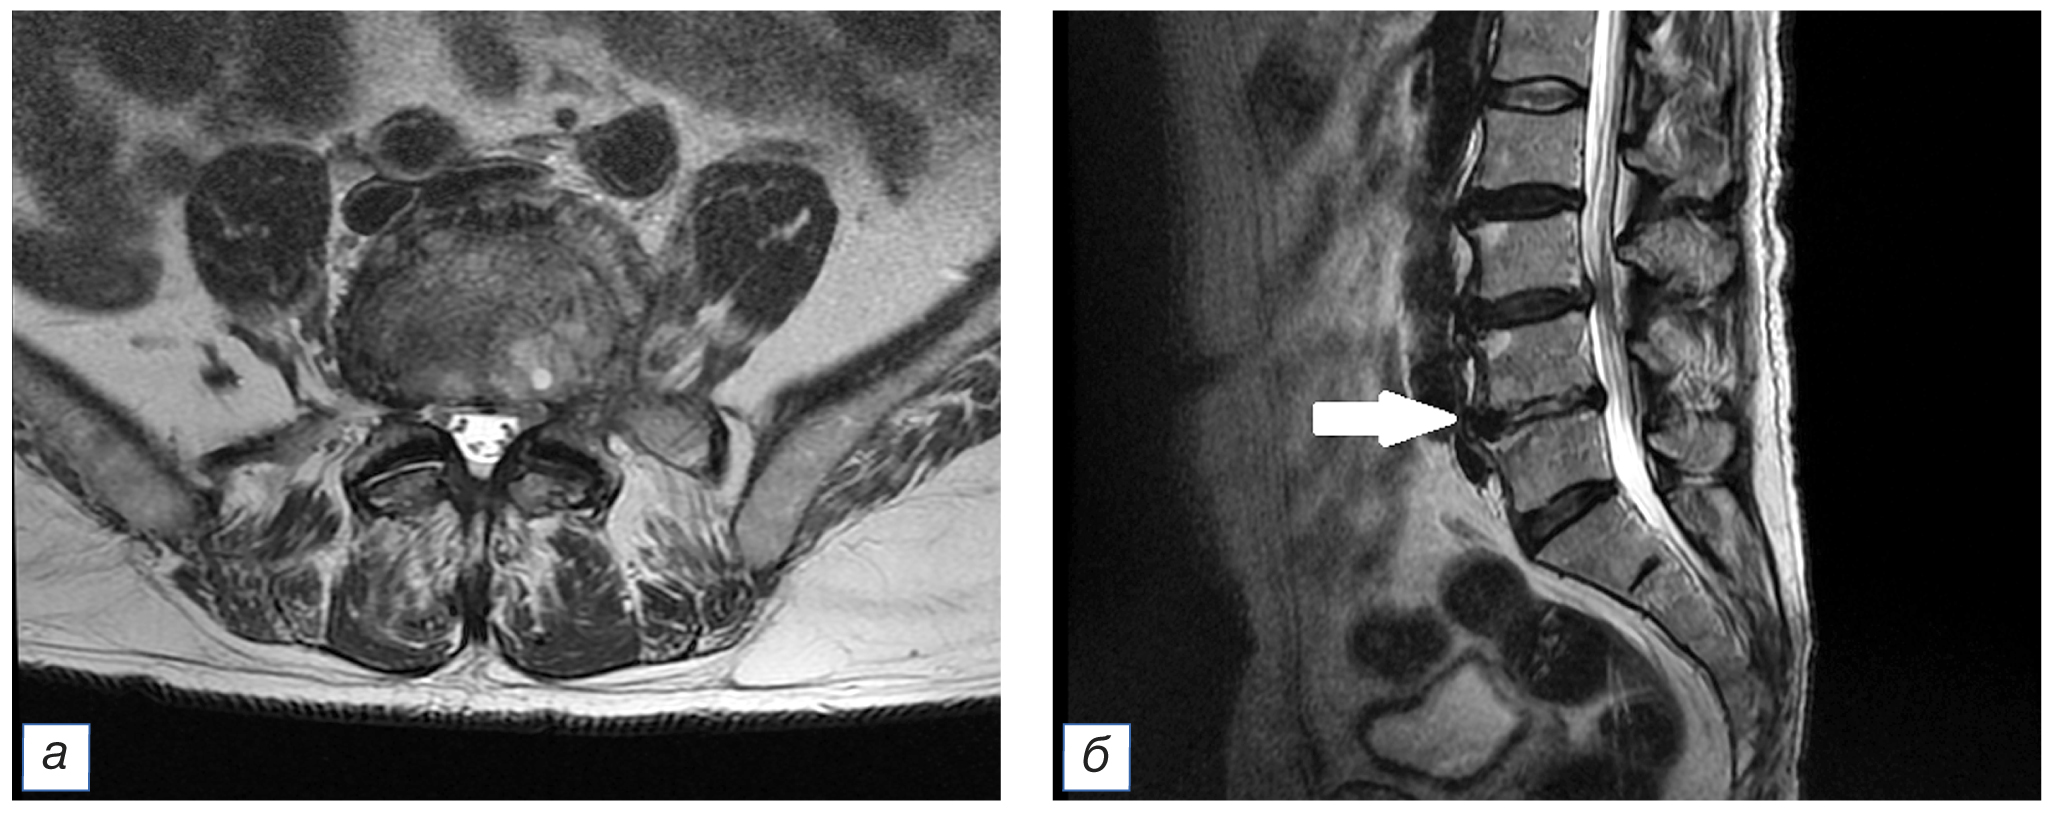

На 25-й день течения COVID-19 у пациента появилась умеренная боль в поясничной области, которая была расценена как проявление неспецифической скелетно-мышечной боли спондилогенного происхождения. Через несколько дней боль в пояснице внезапно приобрела очень интенсивный характер, что стало поводом для повторного выполнения МРТ поясничного отдела позвоночника, где были выявлены признаки выраженных воспалительных изменений диска L4–L5 по типу спондилодисцита и отек паравертебральных мягких тканей (рис. 4). После консультации пациента нейрохирургом была назначена антибактериальная терапия (см. табл. 1) с хорошим клиническим результатом.

Рис. 4. Тот же пациент: магнитно-резонансная томограмма поясничного отдела позвоночника: а — аксиальный срез в режиме Т2-FLAIR на уровне L4–L5; б — сагиттальный срез позвоночного столба в режиме T2-FLAIR. Стрелкой (б) указан очаг спондилодисцита. / Fig. 4. The same patient: magnetic resonance imaging of the lumbar spine: а — axial slice in T2-FLAIR mode at the L4–L5 level; б — sagittal slice of the spinal column in T2-FLAIR mode. The arrow (б) indicates the focus of spondylodiscitis.